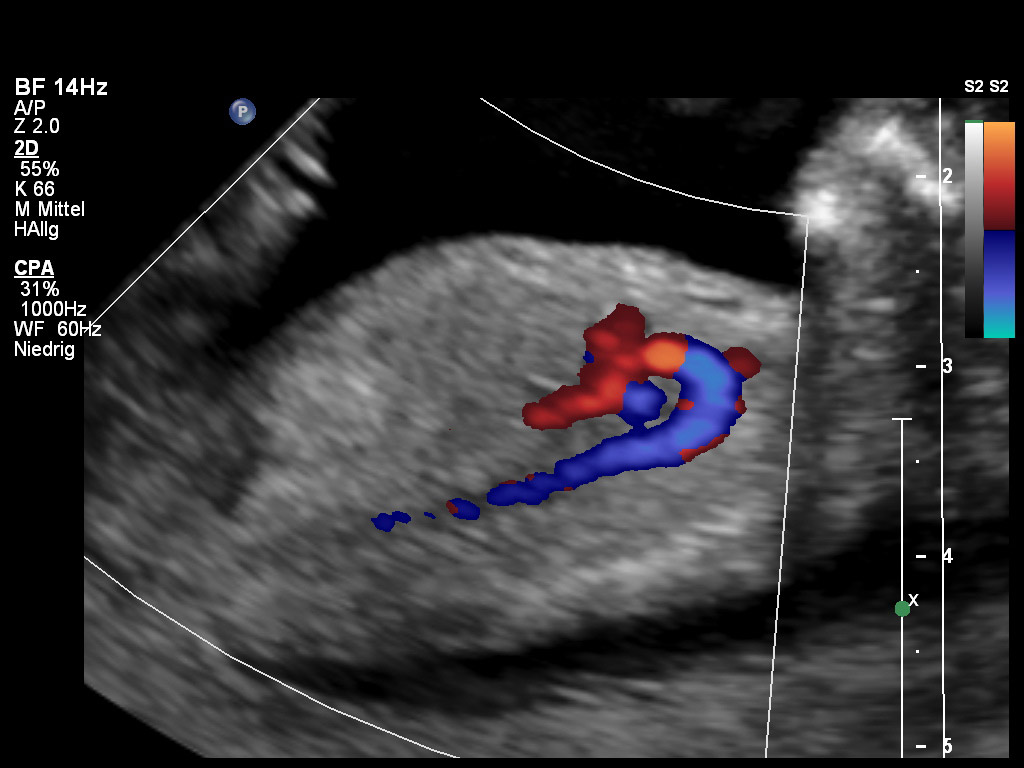

Bei dieser Untersuchung kommen bei uns auch der gepulste Doppler und der Farbdoppler zur Beurteilung des Blutflusses innerhalb des Herzens sowie in den großen herznahen Gefäßen zum Einsatz. Die STIC (Spatial-Temporal Image Correlation) und TUI (Tomographic Ultrasound Imaging) zeigt das Herz auf mehreren Ebenen gleichzeitig, so dass eine bessere räumliche Darstellung gelingt. Dadurch können wir die Herzklappen und Herzwände besser beurteilen, was insbesondere einen Vorteil bei der Einschätzung von Herzfehlern bietet.

Herz mit Farbdoppler SSW 13